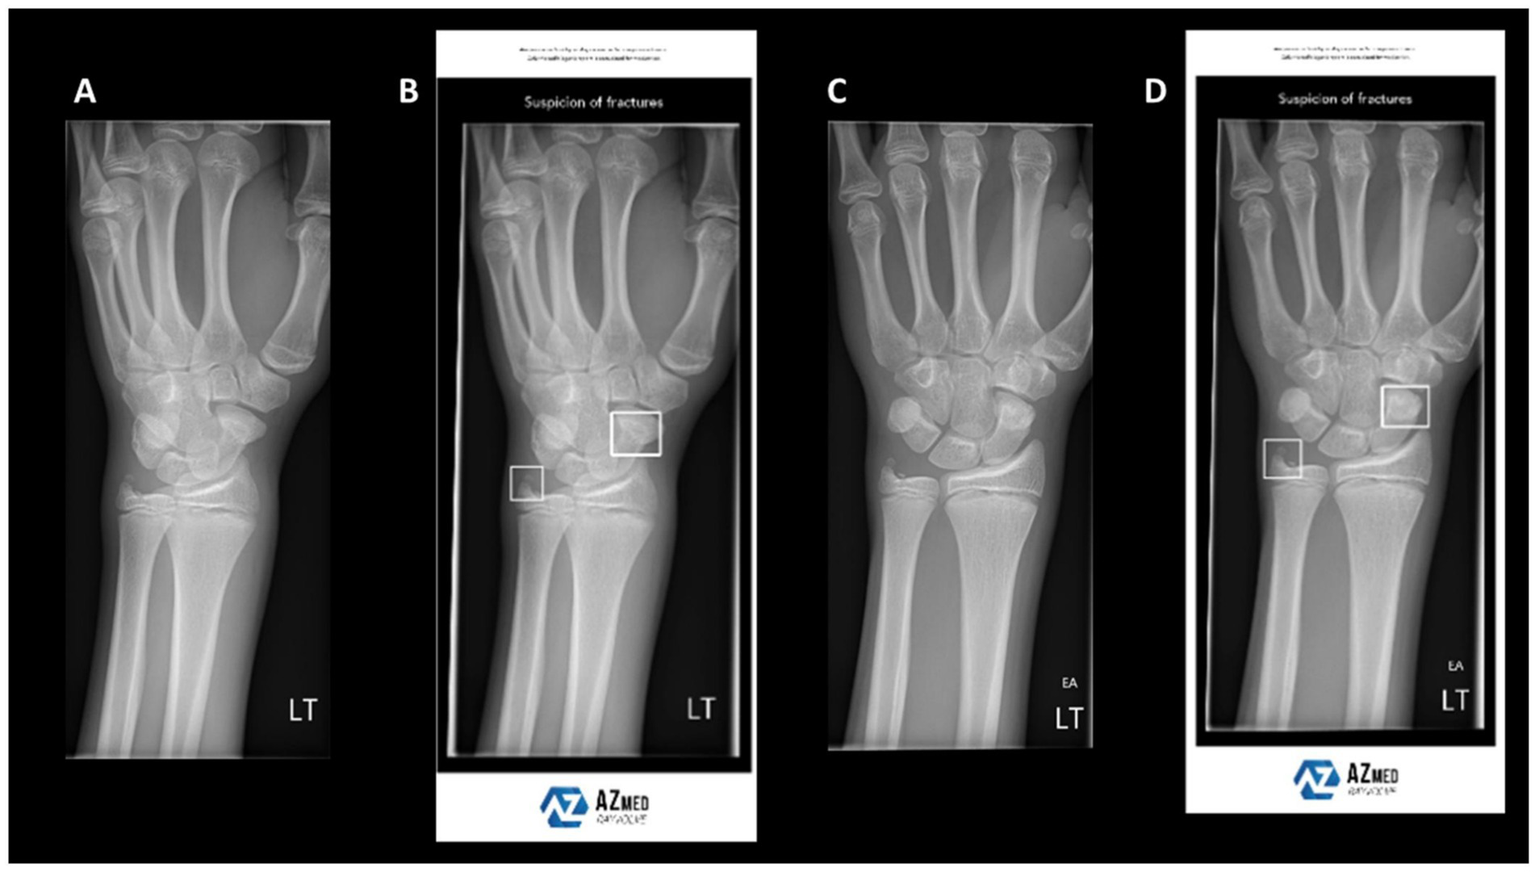

Figure 3

Example wrist radiographs illustrating AI-assisted fracture detection. (A,C) Standard radiographs; (B,D) radiographs with AI-based highlighting of suspected fracture regions. Reproduced under terms of the CC-BY license (39). Copyright 2024, BJR.

Fracture detection and classification represent some of the earliest and most extensively adopted AI applications in orthopaedics. In routine practice, emergency cases are screened using X-rays, whereas complex fractures require CT for detailed anatomical information. However, single-modality imaging has intrinsic limitations, often resulting in missed or misclassified fractures, particularly subtle or complex patterns. Recently, deep-learning models trained on X-rays have been increasingly deployed for fracture recognition. Although these models perform well in selected scenarios, their accuracy declines in the presence of structural overlap or poor image quality (39) (Figure 3). To address these limitations, researchers have fused CT and X-ray data, thereby improving sensitivity and specificity in fracture detection. For example, the FDA-cleared BoneView system automatically annotates suspected fractures on X-rays and cross-validates with CT findings, thereby enhancing detection rates and reporting efficiency in emergency settings. Furthermore, Liu et al. (40) integrated X-rays with demographic and medical history data to predict dissatisfaction after total knee arthroplasty, achieving AUCs of 0.832–0.891 and markedly outperforming models based solely on clinical data. These findings underscore the critical prognostic value of bone-imaging features.